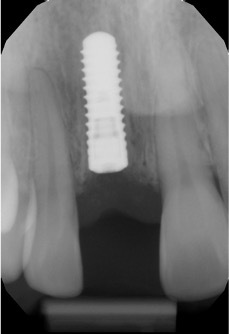

6

Q

What does this image depict?

A

Soft tissue interface